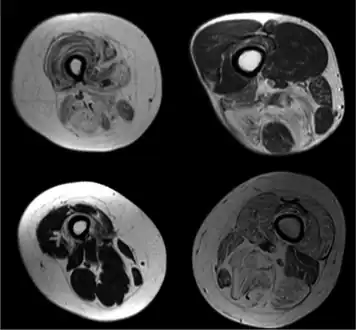

Congenital nemaline myopathy (neuromuscular disorder)

Diagnostic procedures that may reveal muscular disorders include direct clinical observations. This usually starts with the observation of bulk, possible atrophy or loss of muscle tone. Neuromuscular disease can also be diagnosed by imaging, various blood tests and using electrodiagnostic medicine tests[19] including electromyography[20] (measuring electrical activity in muscles) and nerve conduction studies.[21] Genetic testing is an important part of diagnosing inherited neuromuscular conditions.[19]